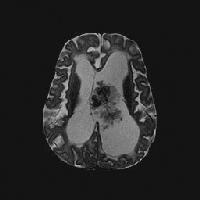

| Axial T2-weighted magnetic resonance image (repetition time, 2883 ms; echo time, 100 ms) shows a lobulated mass with frondlike papillary projections in the left lateral ventricle. The mass is isointense relative to the cortex and has internal hypointense foci that likely represent prominent vessels. Note the associated hydrocephalus and transependymal cerebrospinal fluid flow. |

| Interventricular extension through the foramen of Munro, cerebral aqueduct, or foramen of Luschka or Magendie can occur with a choroid plexus papilloma; this is an ancillary diagnostic sign that is not described with other interventricular tumors. |